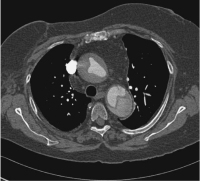

Abbildung 2: CT-Scan mit Kontrastmittelinjektion: Aortendissektion Typ A.

Keywords:

Aortenaneurysma

,

Aortendissektion

CT-Scan

Hypertonie